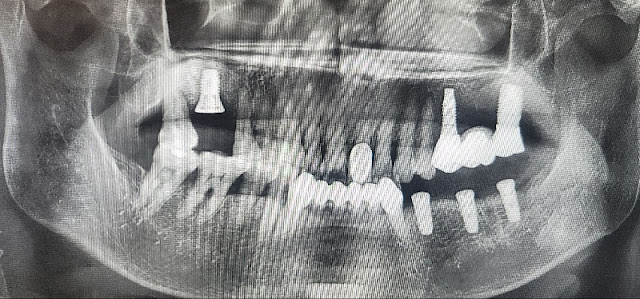

Multiple fixture installing case

When installing multiple fixtures, use a guide in advance to estimate the expected position of the fixtures before incision.